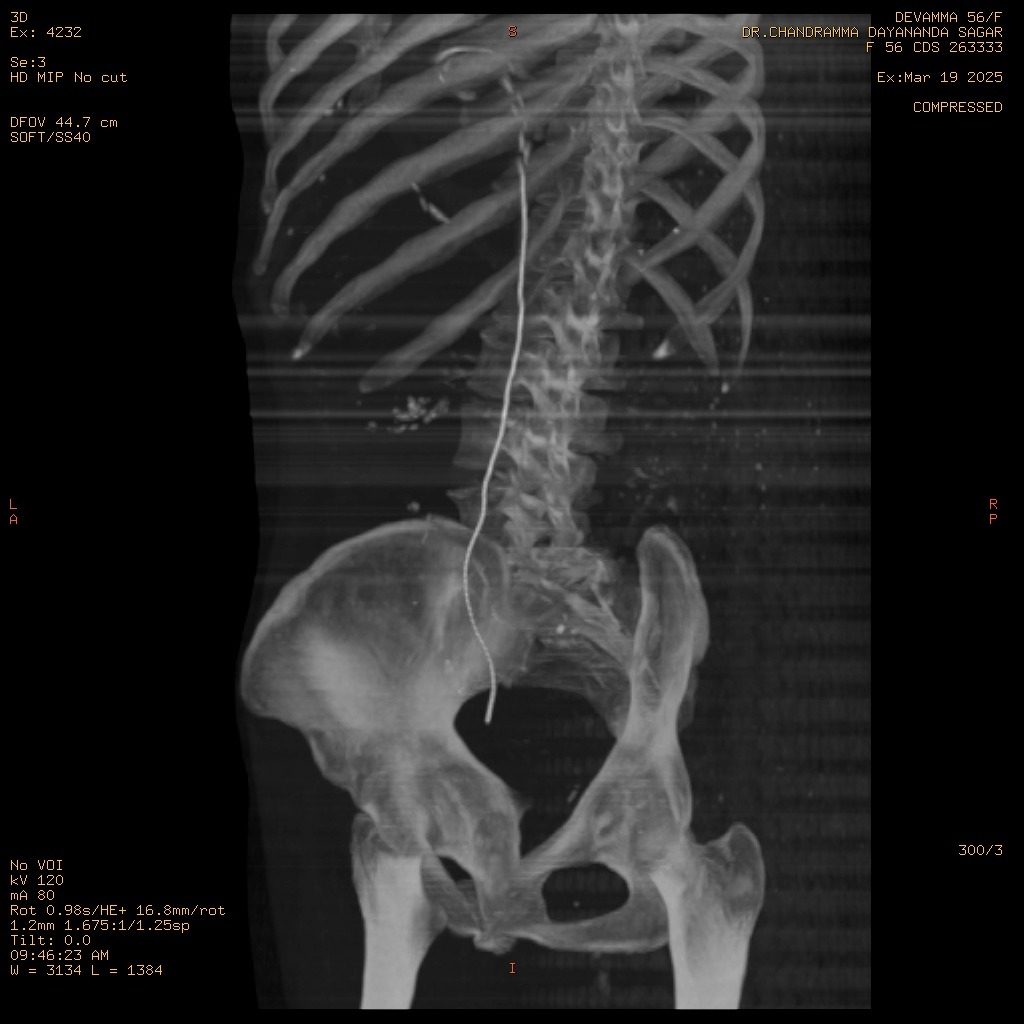

Initial attempts at retrograde left ureteric stenting were hampered by a completely adherent stone, preventing the passage of a standard guide wire. A subsequent thinner, hydrophilic Terumo guide wire was easily negotiated past the obstruction. A diagnostic anomaly was noted when the passage showed an unusual rightward curvature upon successful navigation, leading to suspicion of misplacement.

Following the easy passage of the hydrophilic wire, a 3Fr ureteric stent was passed over it. The stent advanced without resistance, but the proximal pigtail did not coil in the renal pelvis, heightening the suspicion of misplacement. An immediate post-procedure CT scan confirmed the stent's location: the distal end was correctly within the bladder, but the main body and proximal end were located outside the ureter, passing into the Inferior Vena Cava. However, further investigation with MRI of Abdomen revealed that the stent had migrated from the bladder to the left internal iliac vein and reached in the Right Atrium. The patient remained hemodynamically stable. A team meeting was sought, including the opinions of the Cardiologist, Cardiothoracic surgeon, and Urologist, and came to a conclusion that a attempt via endovascular retrieval of the stent. Initial attempts by interventional cardiology via the femoral vein to the Right Atrium failed. Successful retrieval was achieved by an alternative access via the right internal jugular vein, direct entry into the left internal iliac vein. A snare catheter was skillfully deployed to secure the distal end of the DJ stent. The stent was removed successfully without any immediate vascular complication. The patient was monitored in the MICU post-procedure. On the second day post procedure, patient developed mild hematuria and was treated conservatively, and repeat CT KUB with contrast was done, which did not show any remnant fistula.